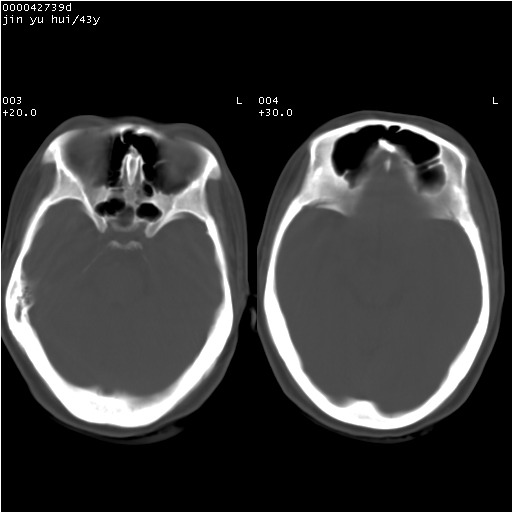

患者 女,43岁。头部外伤26天,经住院治疗,现头痛减轻。申请ct复查,了解颅内情况。

临床诊断:2级脑外伤。

颅脑ct轴位平扫(层厚、层距均为10mm),图像如下:

伴硬膜下水瘤

纵裂旁硬膜下水瘤,左额部头皮肿胀

大脑镰左旁硬膜下血肿慢性期。

大脑镰左旁慢性硬膜下血肿.

大脑镰左旁慢性硬膜下血肿.左额部头皮血肿.

是不是应该为:大脑镰左旁硬膜下血肿吸收期更妥当些;